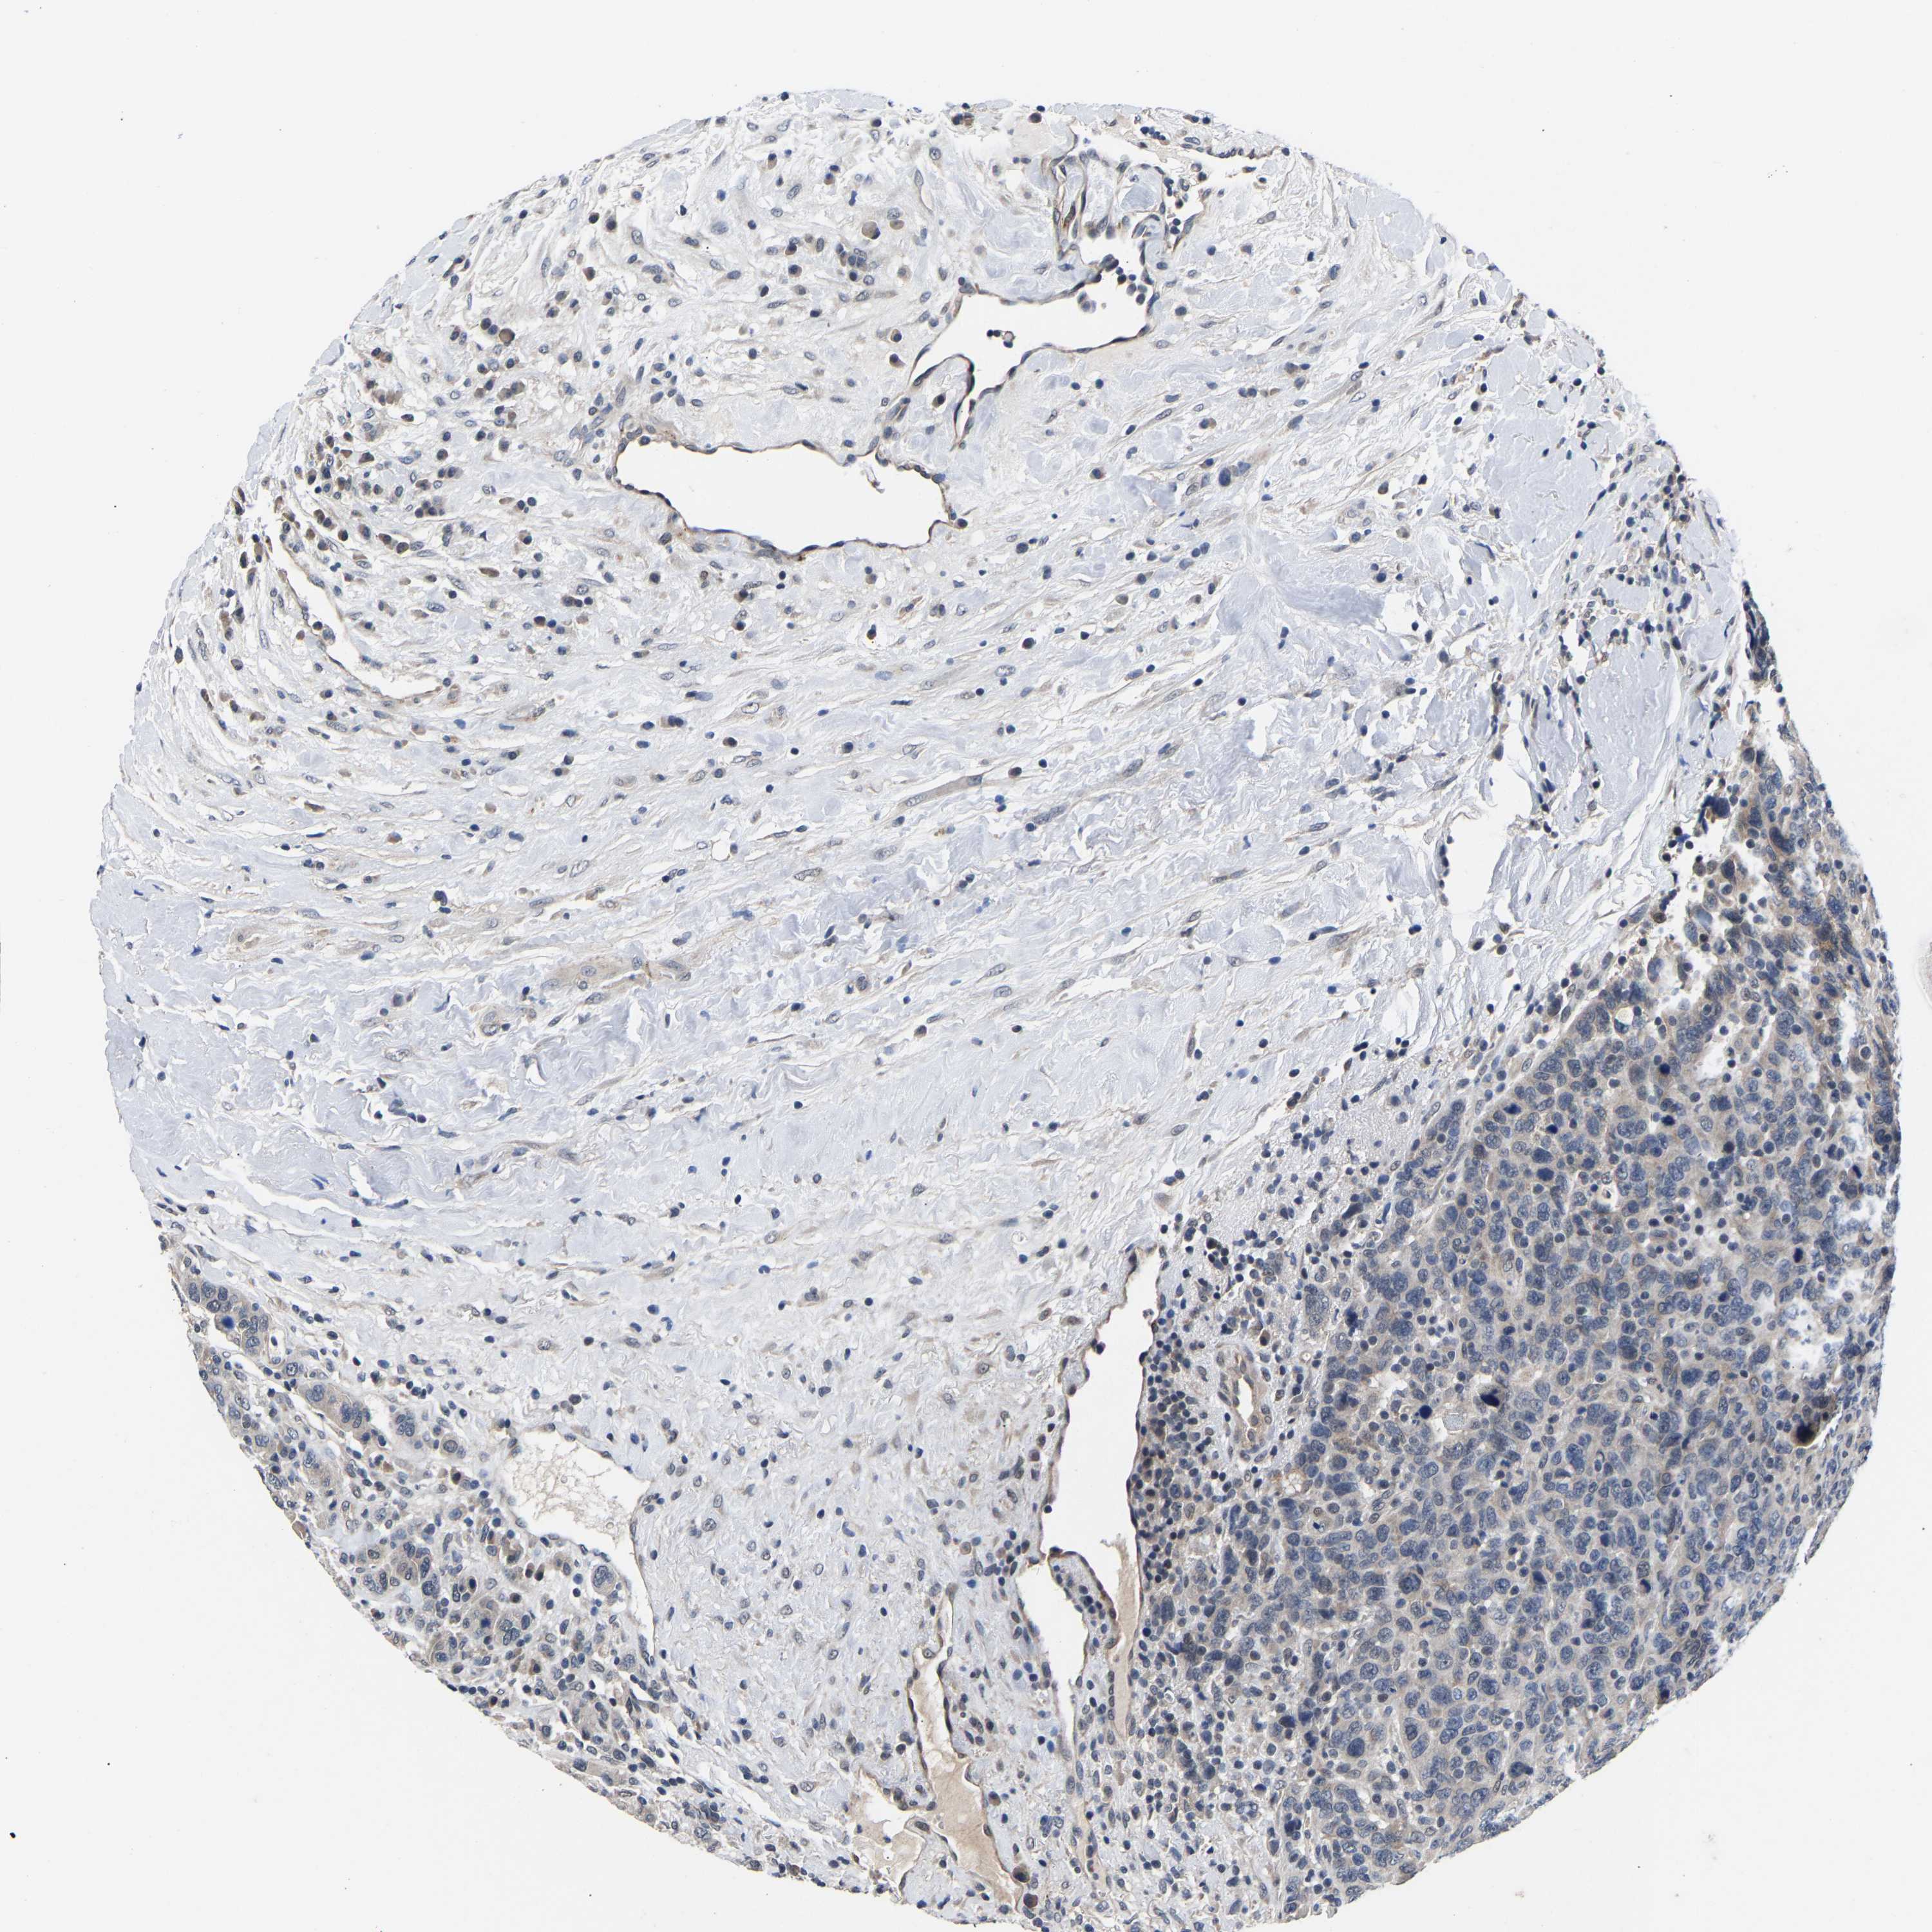

CANCER BREAST CANCER Show tissue menu

BRCA TCGA BRCA VALIDATION PROTEIN EXPRESSION